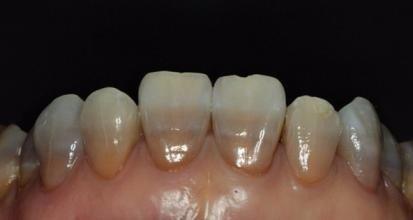

目前,四环素牙的治疗方法主要有四种,即冷光美白、美容冠修复、瓷贴面修复和全瓷冠修复。

四环素牙的牙冠修复治疗适用于所有四环素牙,遮色效果佳。但需磨除较多的牙体组织,可能引起牙髓炎症。有些牙医认为要避免牙髓炎可能,在冠修复前应先将活髓牙变为无髓牙。冠修复目前一般采用的是烤瓷牙冠,其修复后色泽逼真。

四环素牙的贴面治疗可适用于釉质发育不全者,但对于四环素着色严重的牙齿,效果不佳。该治疗需磨除少量牙釉质,在牙表面贴树脂、烤瓷等材料,制作要求较高,形态、色泽较佳,是非常流行的修复方法。

全瓷冠不含有金属层,是由陶瓷切削炼制而成,因此显得更加自然、美观,修复后拥有像真牙一样的色泽。